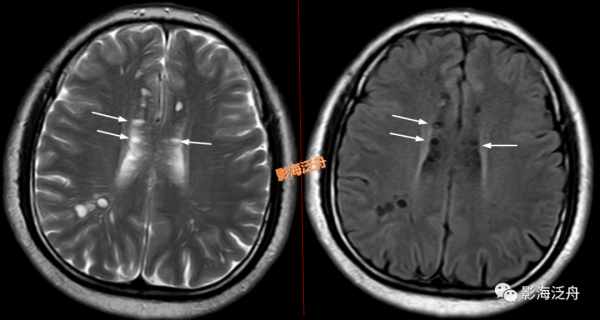

II型-大腦半球型:擴大VR腔隙呈對稱性廣泛分佈於雙側半卵圓中心及皮層下白質區域(黃箭),少位於扣帶回旁(白箭),部分呈類圓形(紅箭頭),部分呈裂隙樣/線樣(藍箭頭),注意綠箭頭所指的VR腔隙邊緣可見Flair高訊號影,這種高訊號可能是區域性液體少量滲漏造成的。

![]()